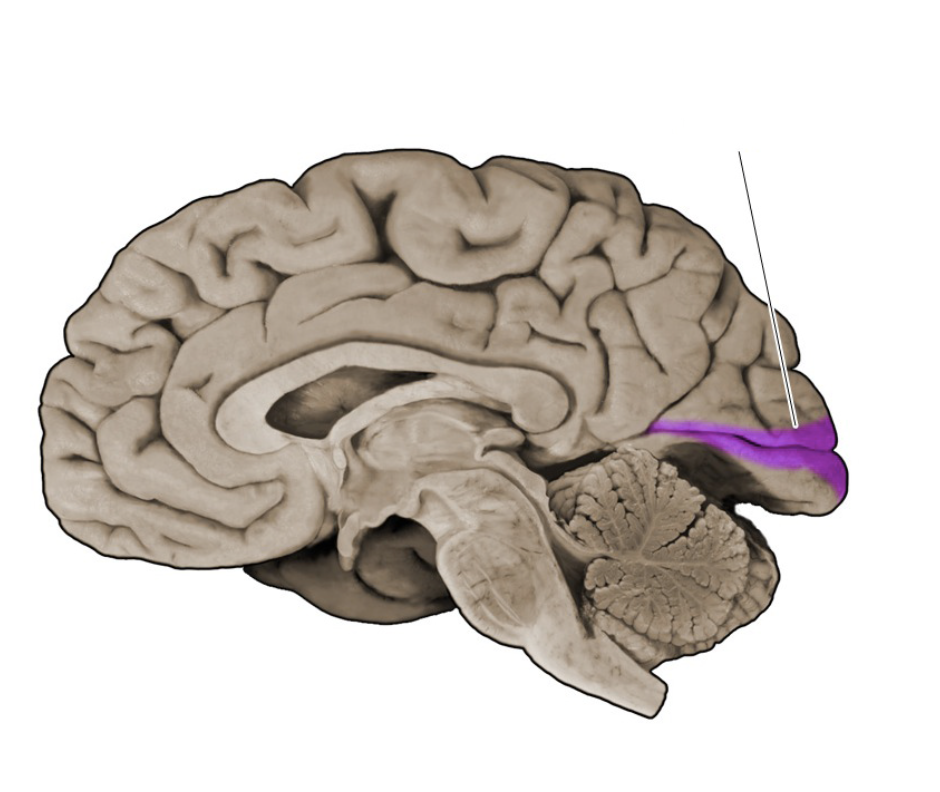

Brodmann's area 17

Sensory cortical area in the banks of the calcarine sulcus (lingual and cuneus gyral formations of the medial occipital lobe); this area corresponds to the primary visual cortex (also known as "striate cortex").

Calcarine sulcus

A prominent sulcus in the medial occipital lobe formed by the cuneus and lingual gyral structures; this sulcus extends roughly horizontally from the parieto-occipital sulcus to its termination in the occipital pole. The calcarine sulcus contains the primary visual cortex (also called the "striate cortex").

Primary visual cortex

Cortical area (Brodmann's area 17; also referred to as the "striate cortex") in the banks of the calcarine sulcus that first receives visual signals from the relevant thalamic nucleus (lateral geniculate nucleus).

Parieto-occipital sulcus

Prominent vertically oriented sulcus on the medial aspect of the hemisphere that divides the parietal and occipital lobes; intersects the anterior terminus of the calcarine sulcus at nearly a right angle.